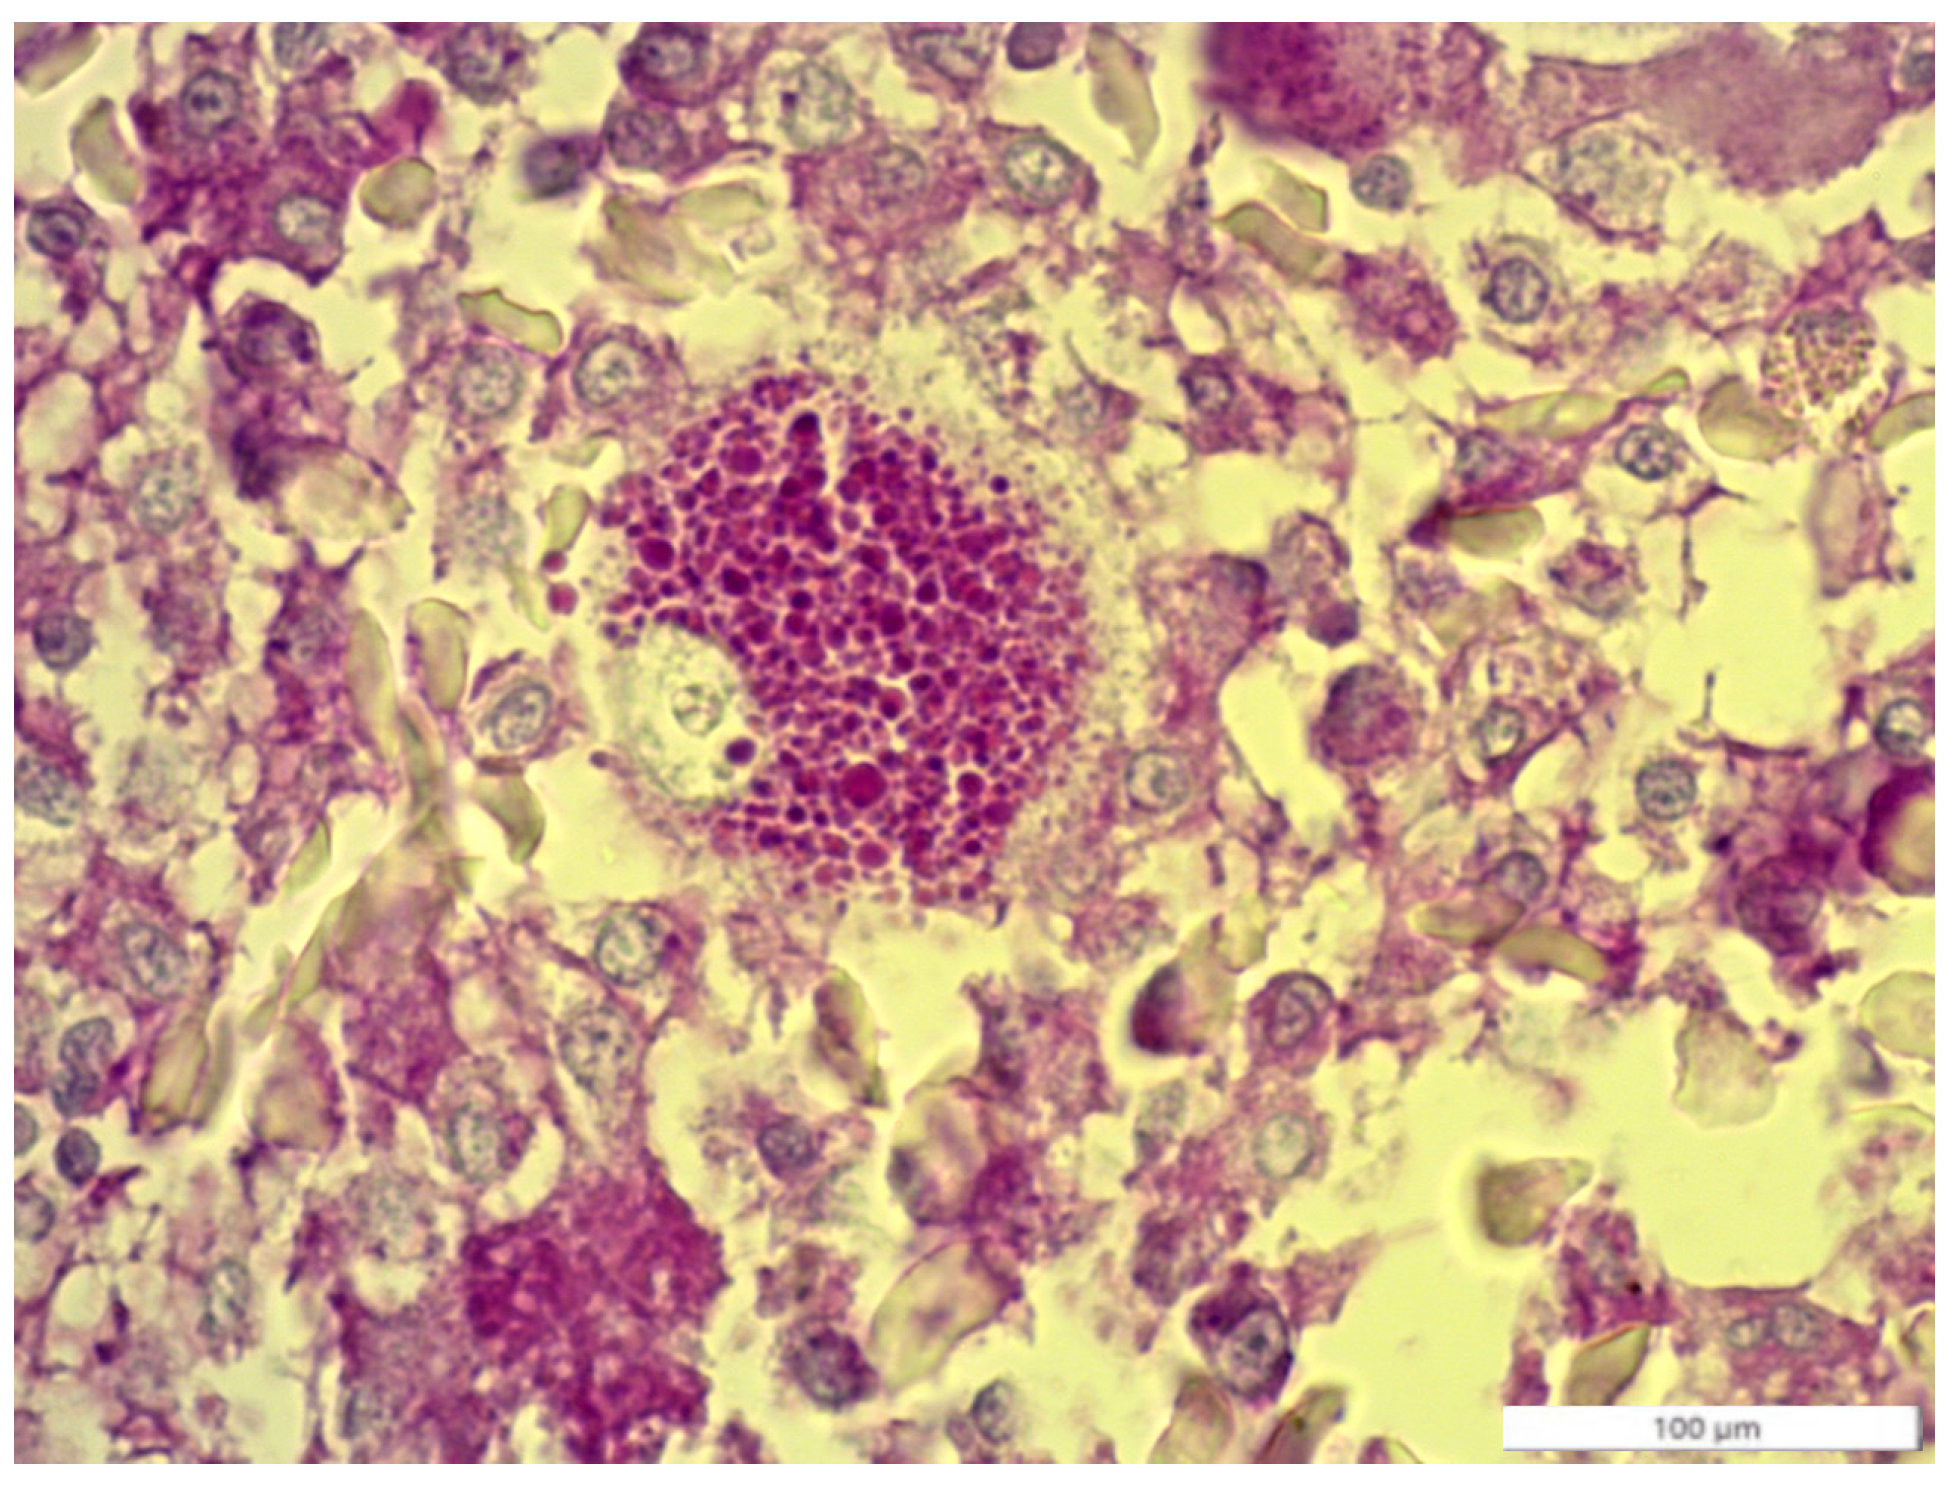

Histological sections stained with EE showed a highly cellular neoplasm consisting of a poorly differentiated population of predominantly spindle to polygonal cells with abundant bi- and multinucleated cells. The cells were medium to large in size. Anisocytosis and anisocaryosis were noted. Irregular, often multiple, prominent nucleoli were observed. Moreover, thanks to the periodic acid–Schiff (PAS) stain, it was possible to observe the presence of large granular cells characteristic of efferent ductules (Figure 2). Based on the cytological and histological appearance, a poorly differentiated extratesticular neoplasm was diagnosed.

Figure 2.

Positive granular cells of efferent ductules. PAS; 100 µm.

This report describes the clinical and pathological findings of a tumour in a male reproductive system in a snake. The male reproductive apparatus in snakes is very complex. Snakes and other squamates have a system of efferent ducts/tubules that have a mixed function, both for the passage of spermatozoa and glandular-like with a secretory function (accessory sex glands) and for the “storage” of sperm. These are androgen-dependent accessory sex glands that secrete the products necessary for viable sperm [24]. The seminiferous tubules empty into the vas deferens, which have an epithelial structure with both simple cuboidal and ciliated cuboidal cells. The nonciliated cubic cells have secretory capacity and are filled with many PAS-positive secretory granules that discharge directly into the ureter at different times of the year [25]. The size of the secretory granules of the renal epithelium peaks at the time of mating and regresses in association with post-spermatogenesis regression [24]. The efferent ductulae are, therefore, an extratesticular portion in continuity with the testicular network and continue with the epididymal duct, which drains into the ureter [26]. Based on these anatomical considerations, the location of this testicular portion and the presence of PAS-positive granulations in the cytoplasm of some large cells, it was possible to identify the origin of the tumour as the intermediate portion between the testis and the kidney (“epithelial portion”), i.e., the area that, in reptiles, starts from the caudal portion of the kidney and continues with the testis.